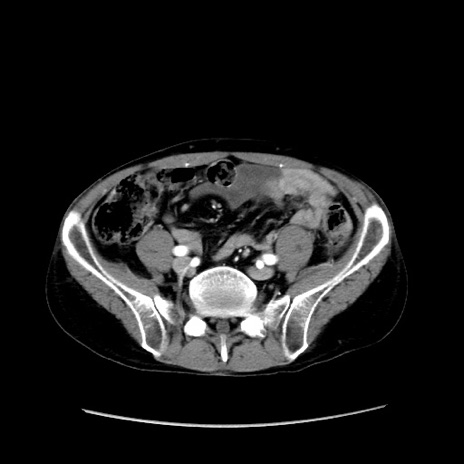

冠状断像

【症例】40歳代 男性

【主訴】腹痛

【現病歴】4時間ほど前に電車に乗車中に臍部上より腹痛出現。徐々に増悪し起立困難となり、救急外来受診。生ものは数日食べていない。今朝お雑煮を食べた。

【身体所見】BT 36.8℃、BP 117/84mmHg、HR 91/min、SpO2 97%、苦悶様、腹部:臍上部広範囲圧痛あり、反跳痛±

【データ】WBC 8100、CRP 0.03